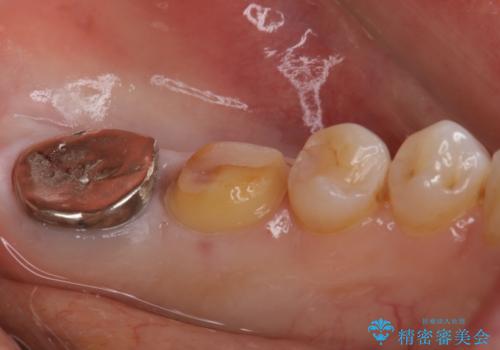

- 他院で、仮歯にしたがセラミックの値段が高すぎると思ったため治療相談も含めて来院された患者様です。

仮歯を新調させていただき、再度虫歯治療を行なって、歯の形を作りセラミックを入れさせていただきました。

フルジルコニアクラウン 7万円(税抜)

仮歯 1万円

にて治療させていただきました。色に関しても喜んでいただき満足されていました。